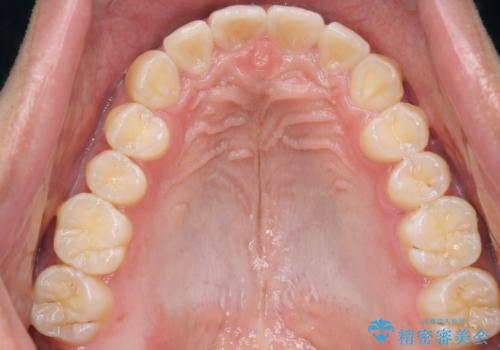

インビザラインによる出っ歯の矯正

- 出っ歯と下の歯のガタガタを主訴に来院されました。

上の奥歯を後方に移動させて、スペースを作り前歯を内側に引っ込める計画としました。

インビザラインによるマウスピース矯正で治療をすることとしました。

インビザラインをしっかり使用していただいたので、スムーズに治療をおえることができました。